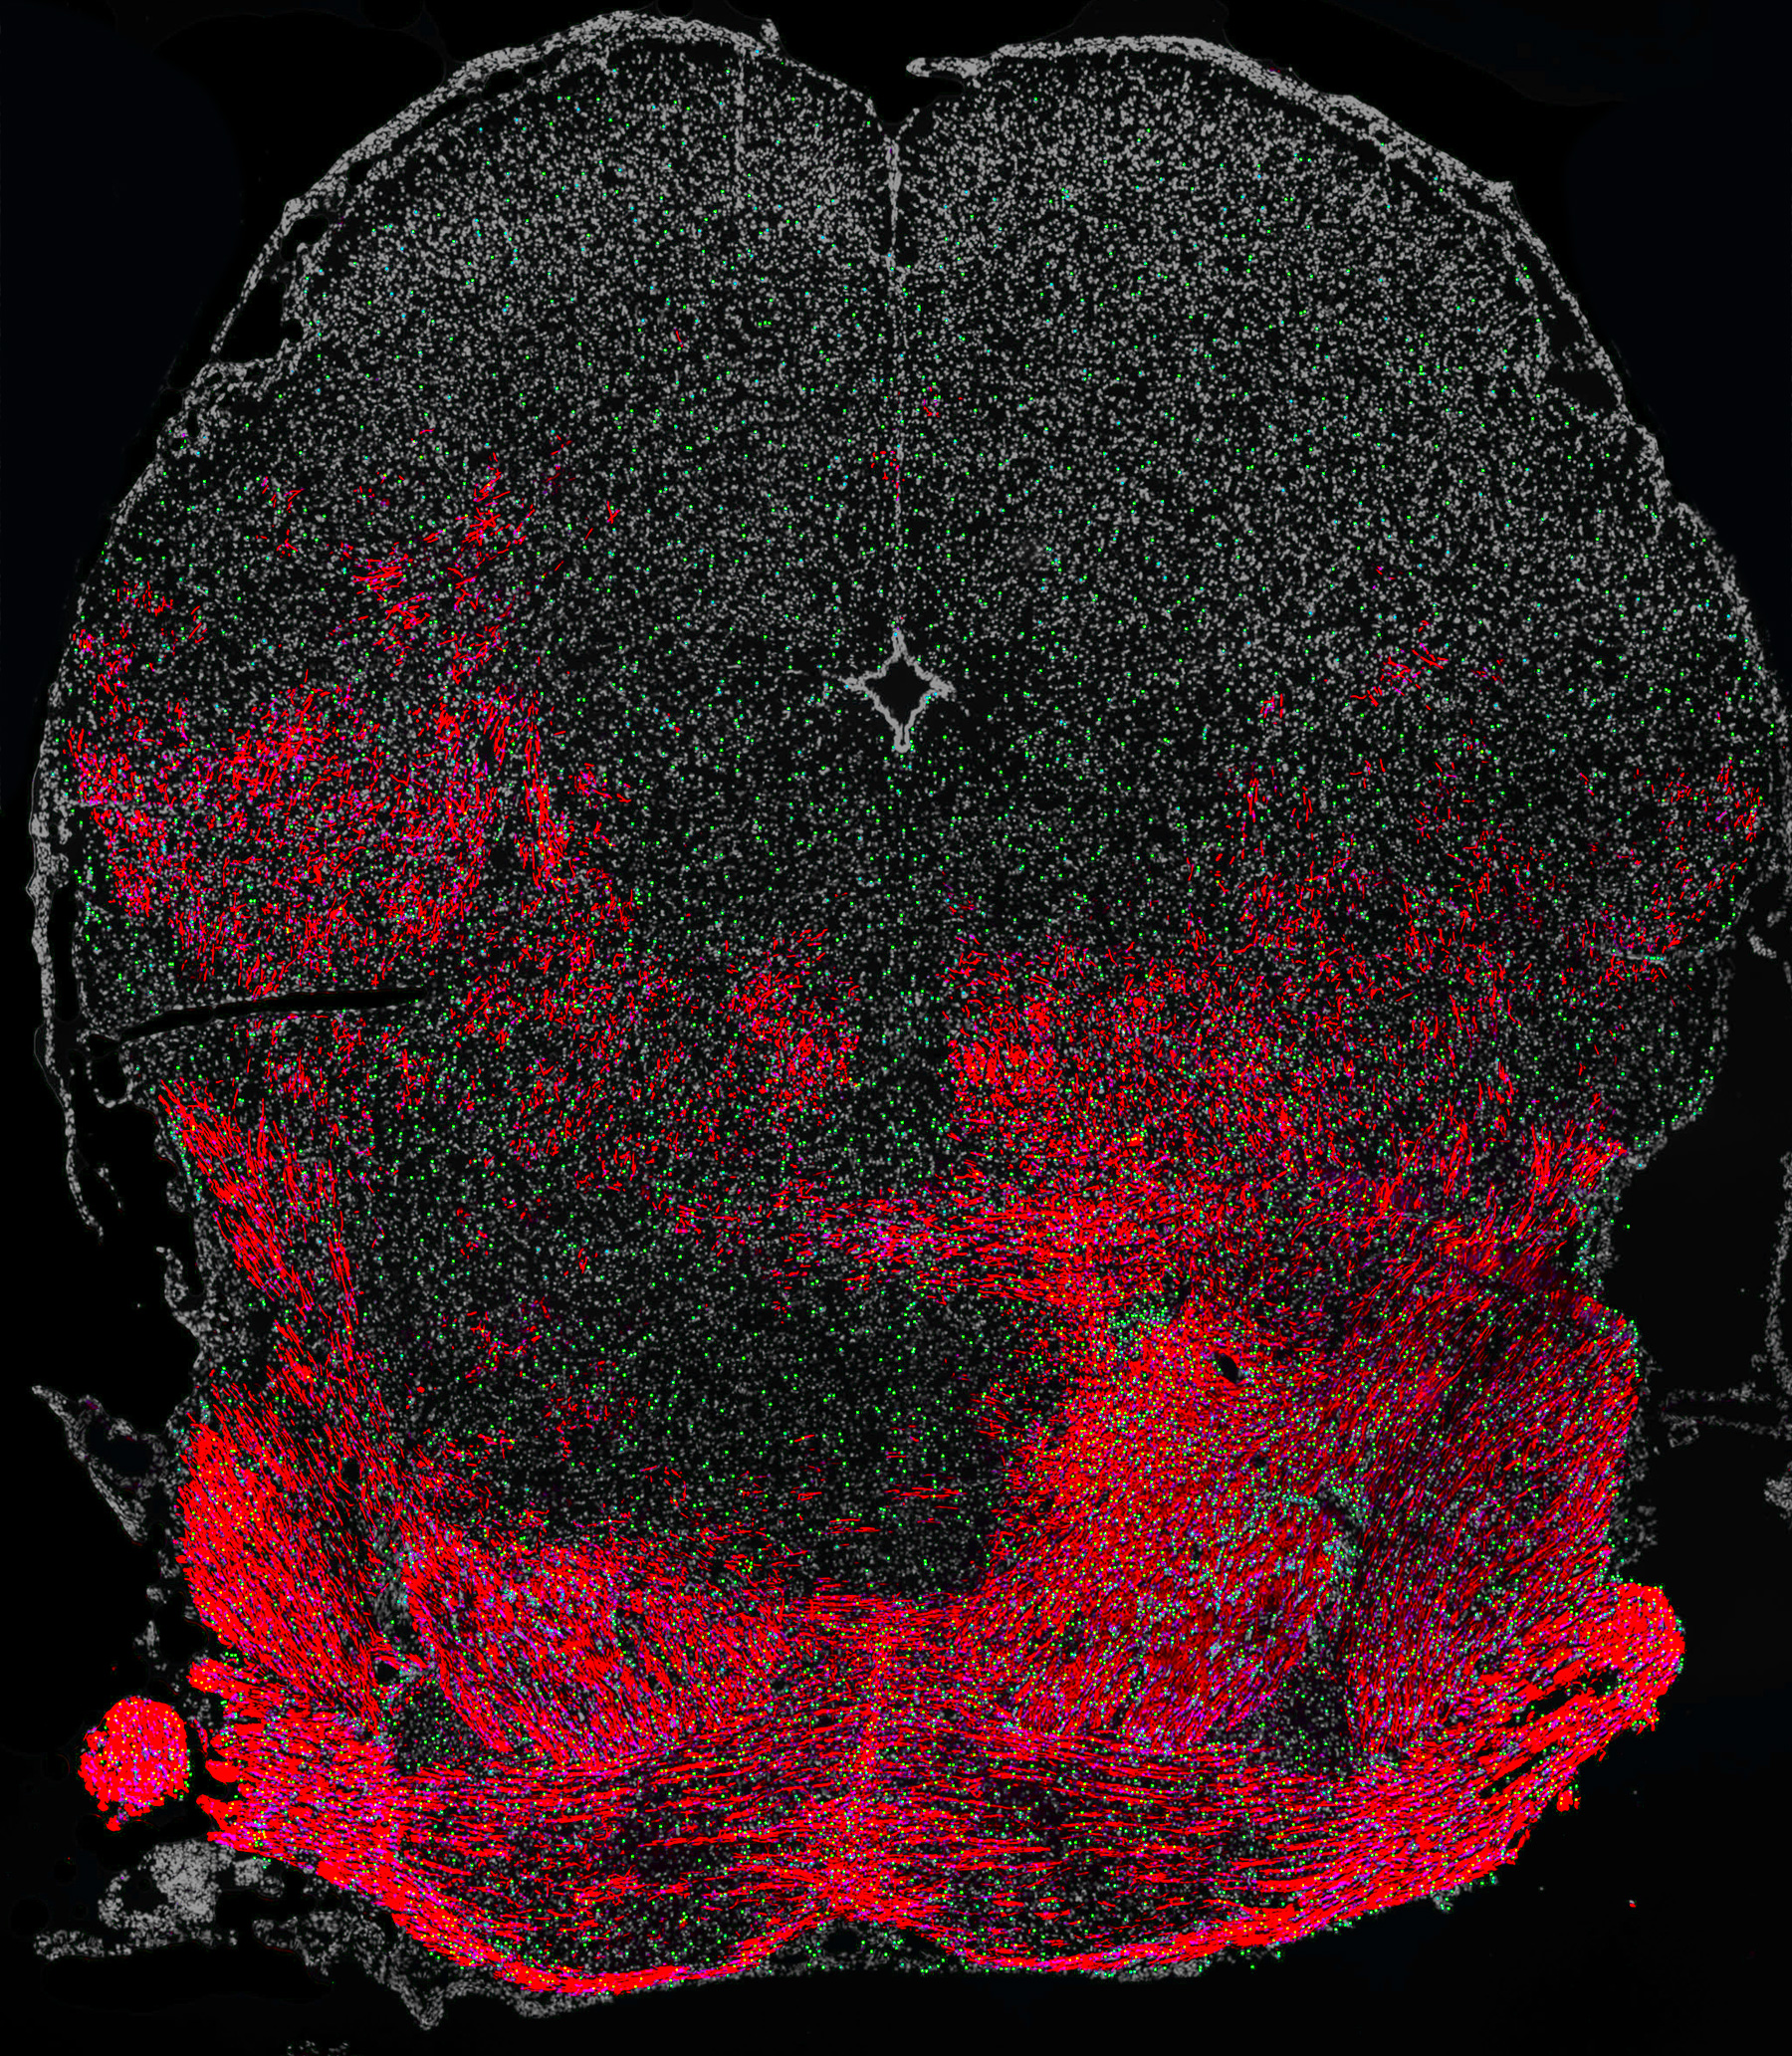

The brainstem of a myelin-deficient mouse that received a transplant of human OPCs a few days after birth and was then treated with the drug solifenacin. Daily treatment enhanced the capacity of human cells (labeled in green) to produce myelin (shown in red), which led to improved hearing in the mouse.

To test whether the drug could boost myelin synthesis, the researchers transplanted human oligodendrocyte progenitor cells into mice that could not make myelin. The result was increased differentiation and myelin synthesis from the transplanted human cells.

Sim explains that it takes a certain amount of time for a signal to go from the ear to the front of the brain: “So in the readout, you get waves that should have a certain time pattern. When there isn’t enough myelin, the signaling slows down. And if you add myelin, you should see the signals speed up.”

The tests showed improvement in the response to auditory signals in animals transplanted with the human oligodendrocyte progenitor cells treated with solifenacin.